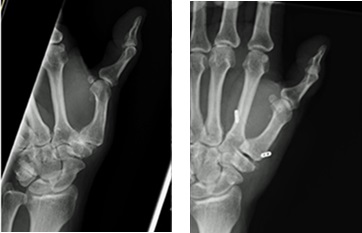

キーンベック病

誘因無く手関節が痛く力が入りにくくなる。XPで月状骨が破壊されてくる病気です。原因はわかりませんが、老人以外は進行してくることが多く積極的な治療が必要です。

治療方法

XP,MRIで病期を決定します。早期で橈骨が尺骨に比べて長い場合は橈骨短縮骨切り術、そうでない場合は当科では血管柄付き骨移植術を行っています。治療成績は非常に良好です。